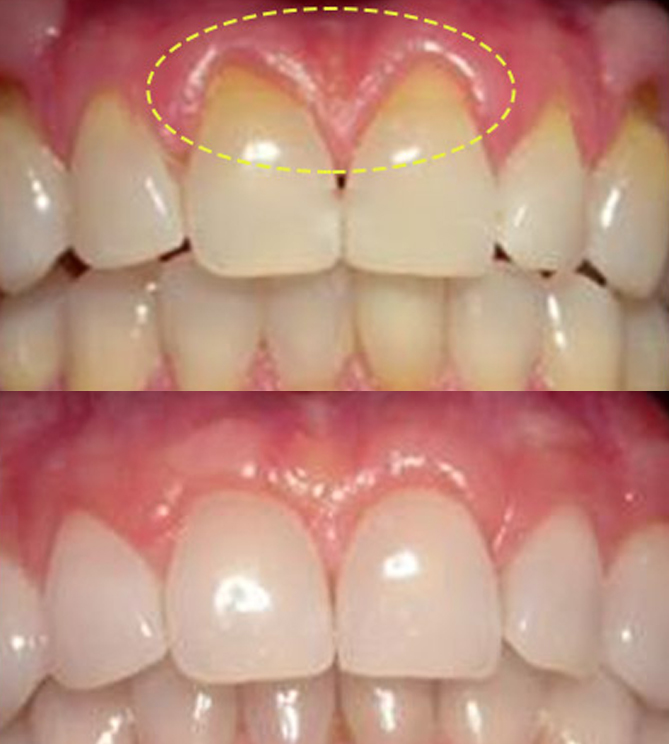

전후사진